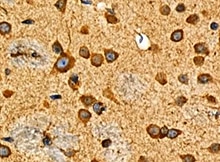

mGluR8 in Human Brain. mGluR8 was detected in immersion fixed paraffin-embedded sections of human brain (hippocampus) using Mouse Anti-Human mGluR8 Monoclonal Antibody (Catalog # MAB5277) at 25 µg/mL overnight at 4 °C. Tissue was stained using the Anti-Mouse HRP-DAB Cell & Tissue Staining Kit (brown; Catalog # CTS002) and counterstained with hematoxylin (blue). View our protocol for Chromogenic IHC Staining of Paraffin-embedded Tissue Sections.

mGluR8 is a Group III metabotropic glutamate receptor. These 7-transmembrane glycoproteins are negatively coupled to adenylate cyclase and expressed presynaptically throughout the brain. mGluR8 shows pronounced expression in the dentate gyrus and CA3 regions of the hippocampus, and is thought to play a role in memory formation. Two splice forms, A and B, differ only in the C-terminal 16 amino acids (aa 893‑909), while splice form C diverges at aa 454 and is truncated prior to the first transmembrane segment. Within the N-terminal extracellular region used as an immunogen (aa 34‑514), human, mouse and rat mGluR8 share 98%‑99% aa identity.